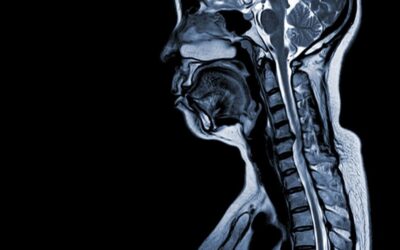

La syringomyélie, terme dérivé du Grec « syrinx » (tube ou flûte) et « myelos » (moelle), désigne la formation d’une ou plusieurs cavités allongées remplies de liquide céphalo-rachidien au sein même de la moelle épinière. Ces cavités, appelées « syrinx », peuvent s’étendre progressivement et comprimer les tissus nerveux environnants.

Parmi les études cliniques en cours, celles portant sur la dynamique des fluides cérébrospinaux suscitent un intérêt particulier. Des chercheurs utilisent des techniques d’IRM de flux pour comprendre précisément comment les anomalies de circulation du liquide céphalo-rachidien contribuent à la formation et à l’expansion des syrinx. Ces connaissances pourraient permettre des interventions plus ciblées et moins invasives.

Pour les formes stables, une surveillance IRM annuelle et des séances de kinésithérapie adaptée suffisent souvent. L’évitement des efforts physiques intenses et le maintien d’un poids santé limitent les risques d’aggravation.